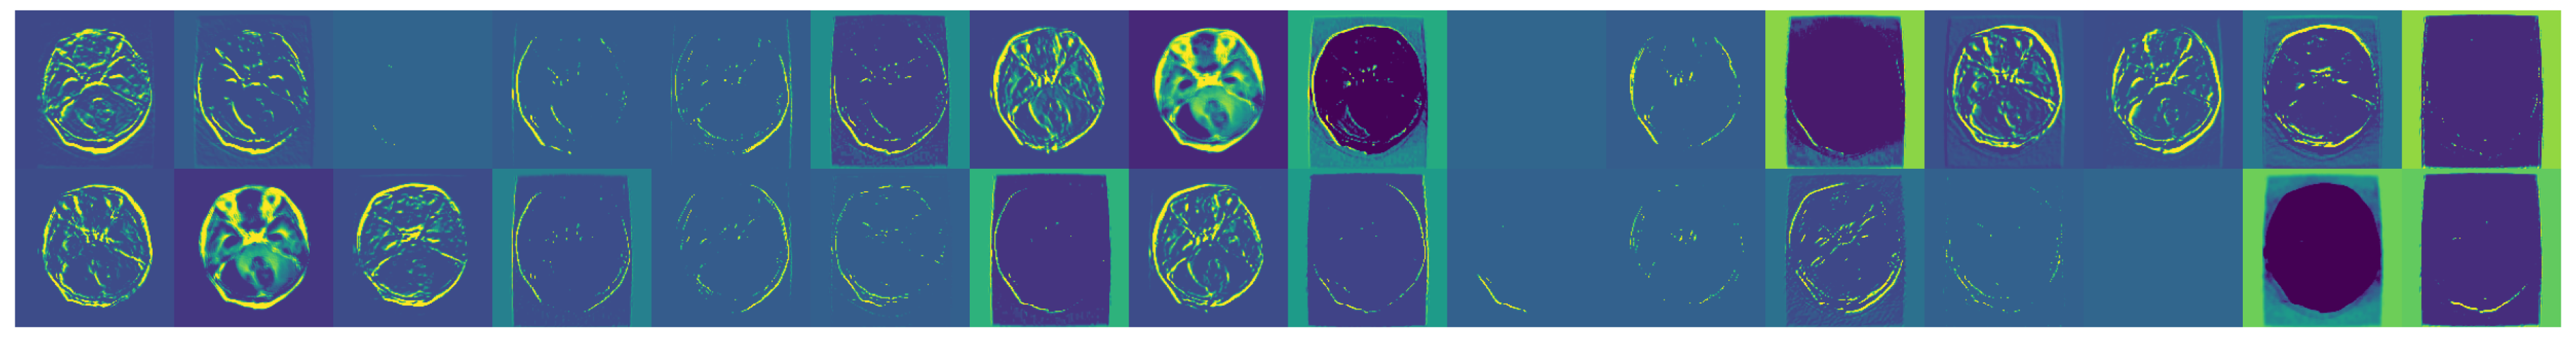

3.1. Dataset Overview

- Glioma: Cancerous tumors in glial cells.

- Meningioma: Non-cancerous tumors originating from the meninges.

- No Tumor: Normal brain scans without detectable tumors.

- Pituitary: Tumors affecting the pituitary gland, which can be either cancerous or non-cancerous.

3.2. Data Preprocessing